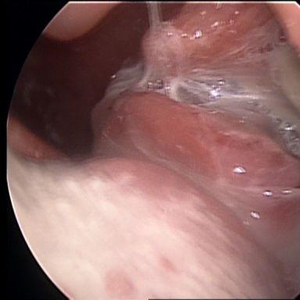

耳鼻喉科主任熊高云主任医师通过检查发现,李先生左侧扁桃体异常肿大,表面有黄白色分泌物,不易去除;右侧扁桃体正常,触摸左侧颌下区淋巴结肿大,活动欠佳,高度怀疑是“扁桃体淋巴瘤”,立即进行喉部增强CT检查。结果显示:左侧扁桃体明显增大,颈动脉区肿大淋巴结,建议手术穿刺活检。

意识到这并不是简单的“扁桃体发炎”,李先生立即接受了扁桃体活检术。熊高云主任在表麻下做了左侧扁桃体活检术,并送病理检查。病理报告结果:首先考虑弥漫大B细胞淋巴瘤。随后,李先生在家人的陪同下转至医院的血液科做进一步治疗。

尤其是单侧扁桃体肿大,且表面粗糙,容易出血,质地硬,甚至出现溃疡、坏死,就需要引起高度重视,考虑是否为扁桃体恶性肿瘤。